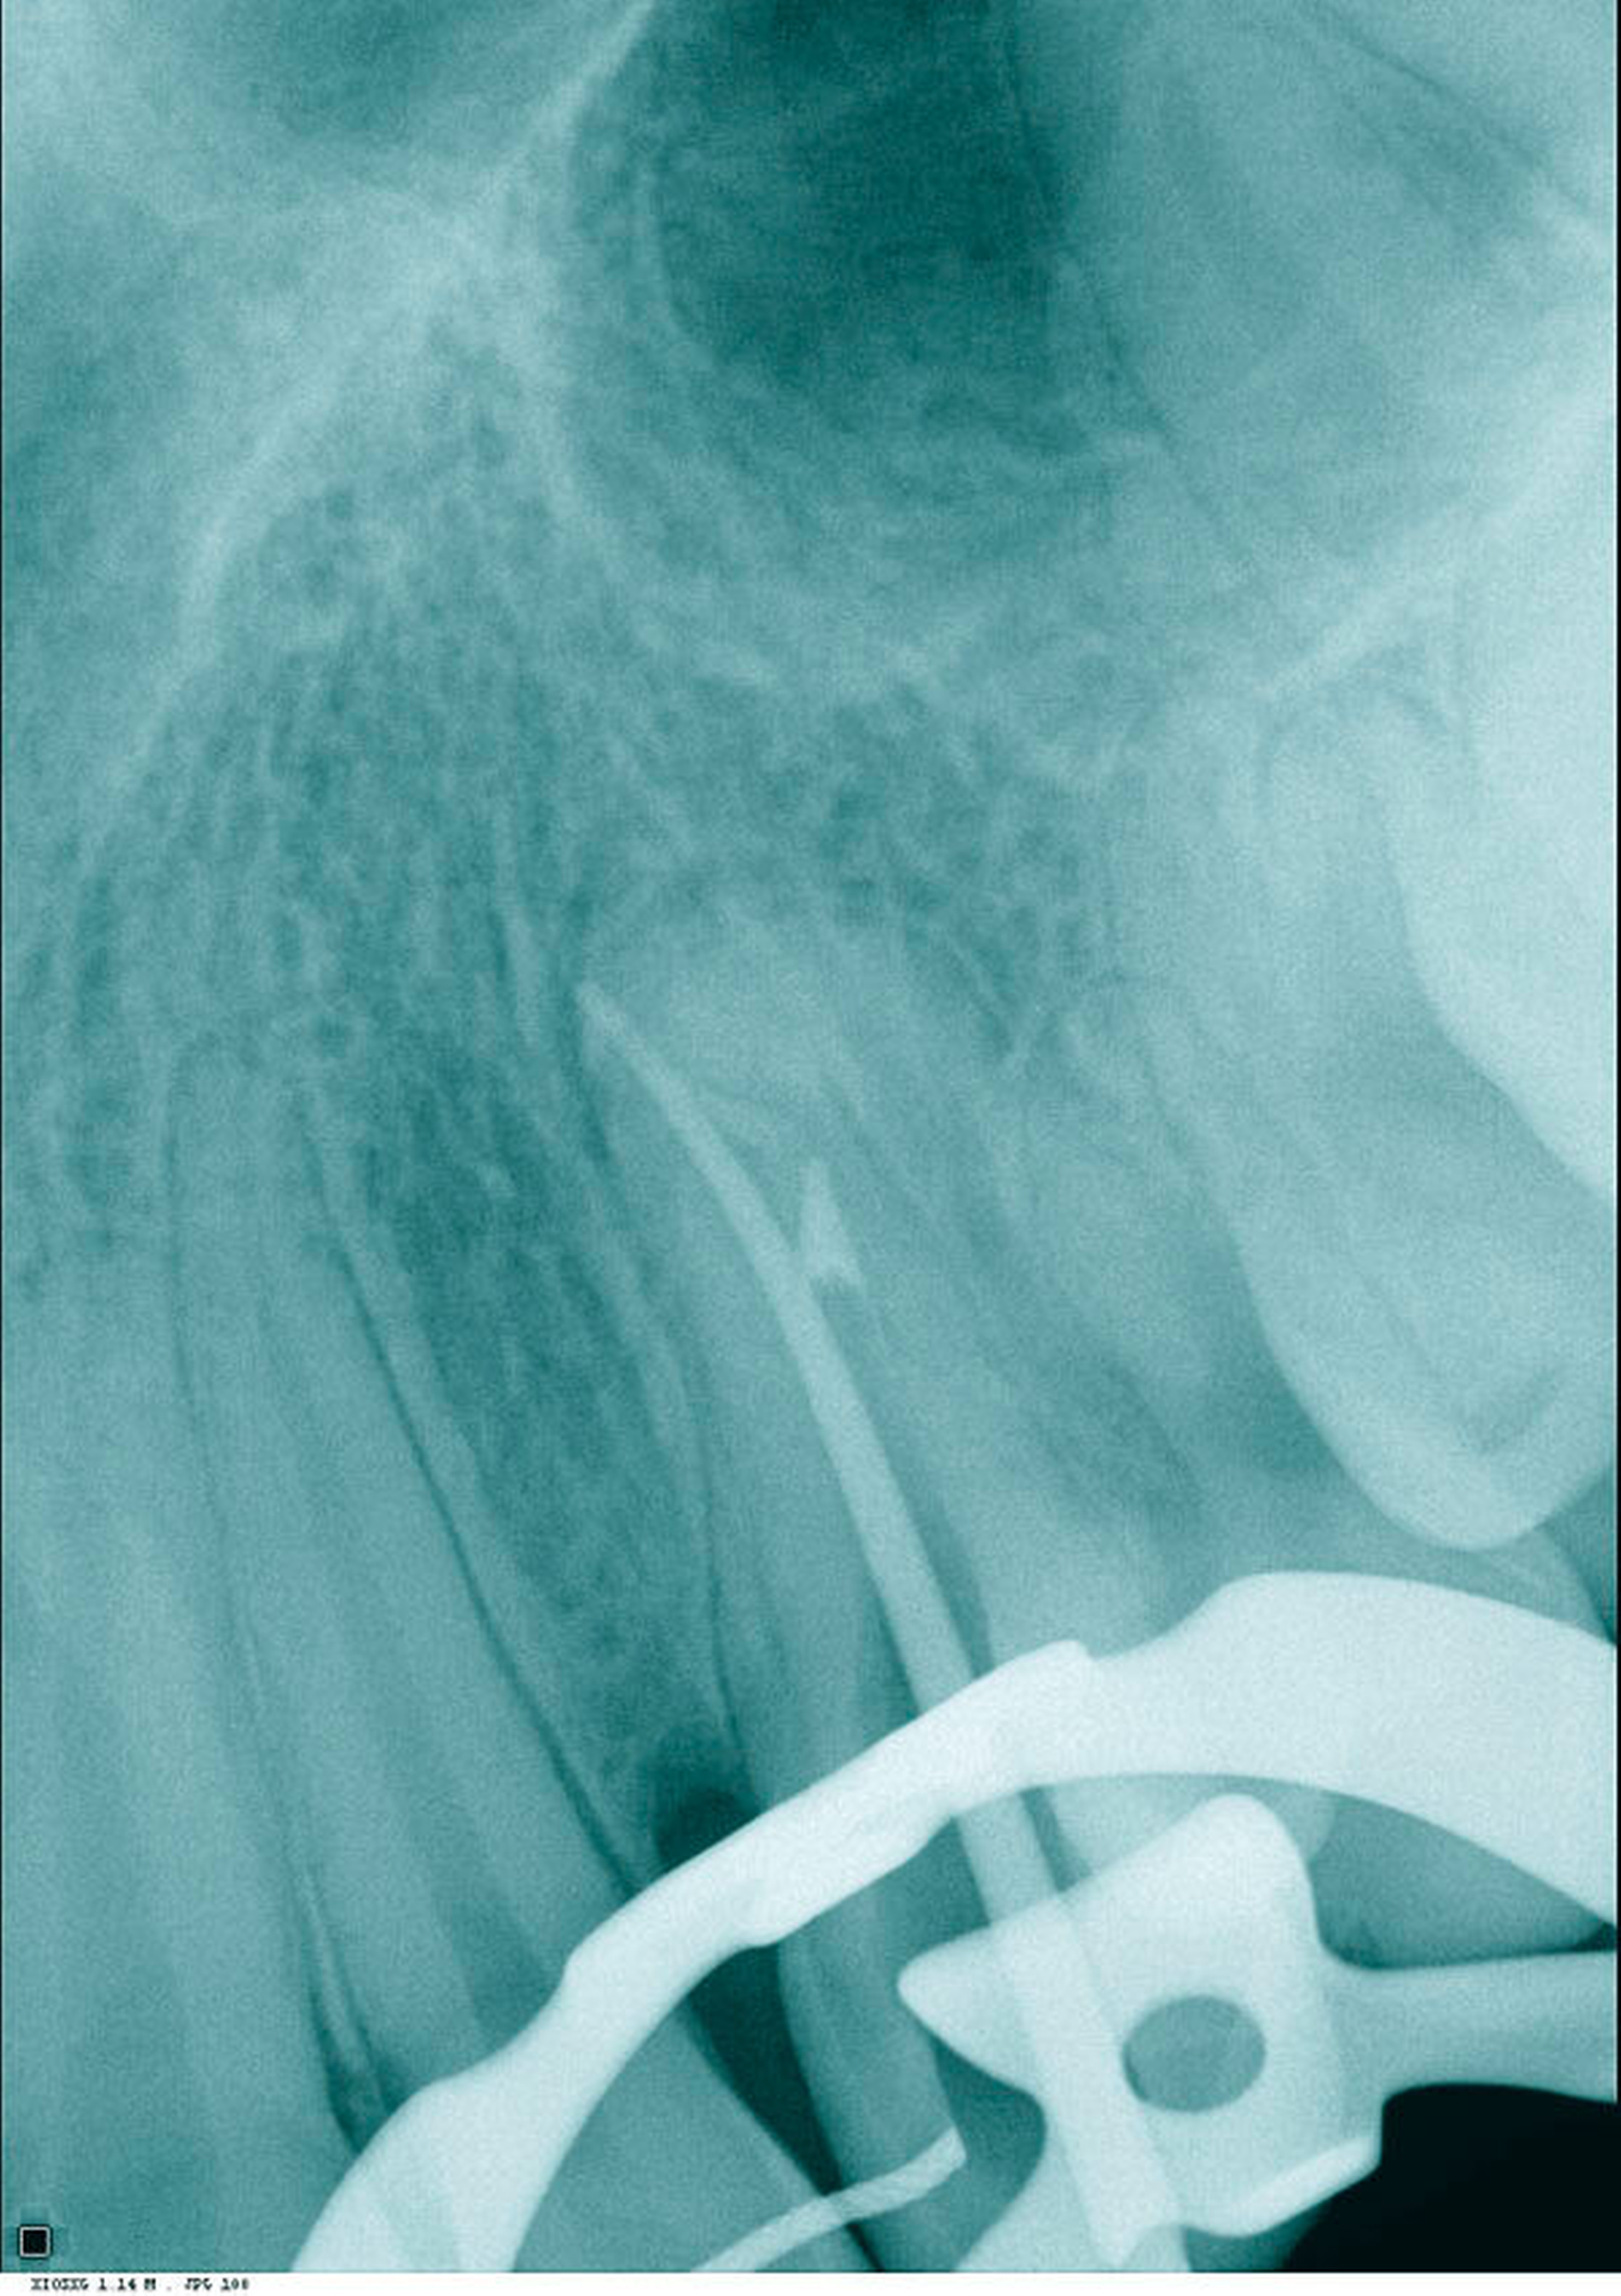

Es erfolgte die Inspektion unter dem OP-Mikroskop. Klinisch zeigte sich kein Anhalt auf Kanalstrukturen. Es erfolgten zwei zeitintensive Sitzungen, in denen der Wurzelkanal nicht dargestellt werden konnte und der Zahn, trotz größter Vorsicht und Verwendung des Mikroskops, perforiert wurde. Die Perforation war vestibulär im mittleren Kanaldrittel nach einer Länge von 18 mm lokalisiert (Abbildungen 3 und 4). Die Therapieentscheidung fiel daraufhin zugunsten einer „Guided Endodontics“-Behandlung.

In der folgenden Sitzung wurde die Schiene angepasst (Abbildung 10), die Trepanationsöffnung ergänzt und die Bohrung mittels Endoseal-Bohrer auf die zuvor am DVT geplante Tiefe vorgenommen. Nach erfolgter Bohrung wurde der Kofferdam angebracht und das erschlossene Kanalsystem mit einer ISO 10 C-Feile sondiert (Abbildung 11). Die Endometrie ergab 23,5 mm. Eine Röntgenkontrastaufnahme mit einer ISO 15 K-Feile wurde angefertigt (Abbildung 12). Die mechanische Wurzelkanalpräparation erfolgte mit Reciproc Blue 25 und 40 (VDW, München), die Desinfektion mit NaOCl 5 Prozent und EDTA 17 Prozent. Die Perforation wurde mit Total Fill BC Root Repair Material (FKG, La Chaux-de-Fonds, Schweiz) abgedeckt (Abbildung 13). Im Anschluss wurde eine Masterpointaufnahme angefertigt (Abbildung 14), der Wurzelkanal mit Total Fill BC Points und Sealer (FKG, La Chaux-de-Fonds, Schweiz) biokeramisch abgefüllt (Abbildung 15) und adhäsiv verschlossen. Bei der klinischen Nachuntersuchung nach vier Wochen war der Zahn symptomlos.